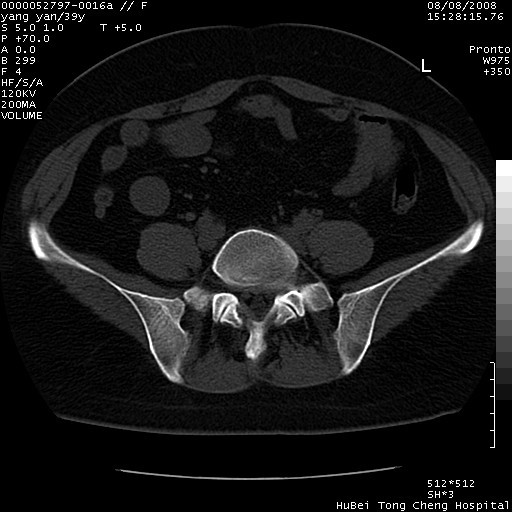

患者 女,39岁。因外伤检查,偶然发现。

典型!双侧骶髂关节致密性骨炎。

典型!病变主要累及双侧髂骨。常见于育龄期妇女。

致密性骨炎,一般不跨越关节面,可是这个骶骨关节面也有硬化。

髂骨致密性骨炎系一种以骨质硬化为特点的非特异性炎症,有高度致密的骨硬化现象,尤其以髂骨下2/3更为明显,但关节间隙则无改变。因位于骶髂关节,且该关节症状明显,故又称之为“骶髂关节致密性骨炎”。 本病90%以上为中年女性,以妊娠后期、尤其分娩后为多见,亦可见于尿路或女性附件慢性感染后,或盆腔内其他感染。此外,臀骶部的外伤亦可诱发或引起本病。  妊娠、分娩及外伤均可引起骶髂关节韧带的撕裂而易使局部的血供受阻。因此早期局部呈现充血、水肿及渗出增加等,渐而局部出现增生与变性反应,随着胶原纤维的致密化而向硬化演变;血管形成厚壁血管,易闭塞而引起髂骨耳状面处缺血和缺氧,骨质呈现硬化性改变,以致手术时局部出血较少。骶髂关节囊壁显示纤维增生、弹性降低及松动样改变。继发于盆腔内炎症者亦出现相类似的病理改变,可能系细菌内毒素作用所致。